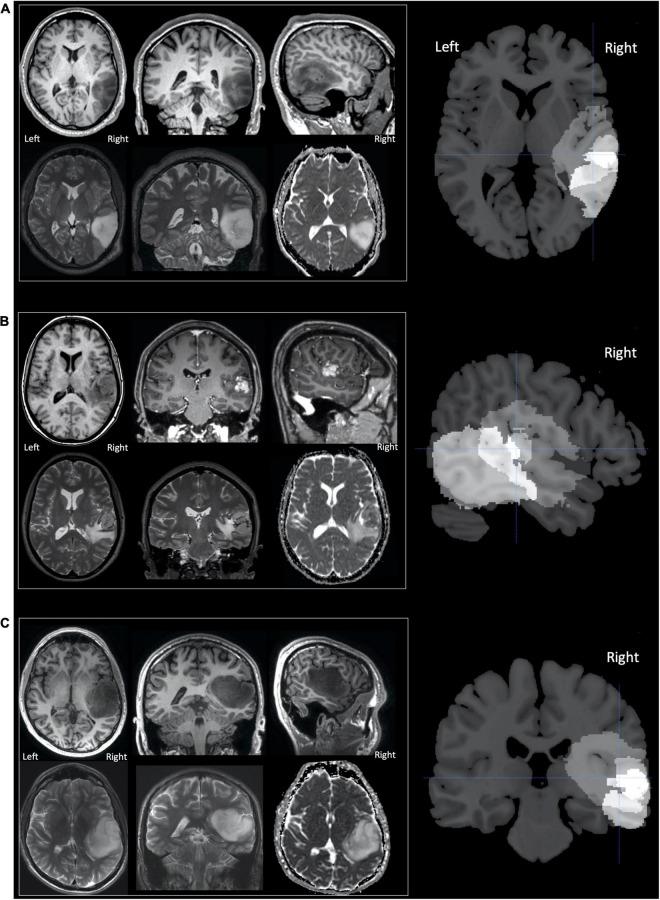

Using fMRI, we investigated how right temporal lobe gliomas affecting the posterior superior temporal sulcus alter neural processing observed during speech perception and production tasks. Behavioural language testing showed that three pre-operative neurosurgical patients with grade 2, grade 3 or grade 4 tumours had the same pattern of mild language impairment in the domains of object naming and written word comprehension. When matching heard words for semantic relatedness (a speech perception task), these patients showed under-activation in the tumour infiltrated right superior temporal lobe compared to 61 neurotypical participants and 16 patients with tumours that preserved the right postero-superior temporal lobe, with enhanced activation within the (tumour-free) contralateral left superior temporal lobe. In contrast, when correctly naming objects (a speech production task), the patients with right postero-superior temporal lobe tumours showed higher activation than both control groups in the same right postero-superior temporal lobe region that was under-activated during auditory semantic matching. The task dependent pattern of under-activation during the auditory speech task and over-activation during object naming was also observed in eight stroke patients with right hemisphere infarcts that affected the right postero-superior temporal lobe compared to eight stroke patients with right hemisphere infarcts that spared it. These task-specific and site-specific cross-pathology effects highlight the importance of the right temporal lobe for language processing and motivate further study of how right temporal lobe tumours affect language performance and neural reorganisation. These findings may have important implications for surgical management of these patients, as knowledge of the regions showing functional reorganisation may help to avoid their inadvertent damage during neurosurgery.

我们使用功能磁共振成像(fMRI)研究了影响颞上沟后部的右侧颞叶胶质瘤如何改变在言语感知和产生任务中观察到的神经处理过程。行为语言测试表明,三名术前患有2级、3级或4级肿瘤的神经外科患者在物体命名和书面文字理解领域具有相同模式的轻度语言障碍。在进行语义相关性的听词匹配(一项言语感知任务)时,与61名神经典型参与者和16名保留右侧颞上后叶的肿瘤患者相比,这些患者在肿瘤浸润的右侧颞上叶表现出激活不足,而在对侧(无肿瘤的)左侧颞上叶则有增强激活。相比之下,在正确命名物体(一项言语产生任务)时,患有右侧颞上后叶肿瘤的患者在听觉语义匹配期间激活不足的同一右侧颞上后叶区域的激活程度高于两个对照组。与八名右侧半球梗死未累及右侧颞上后叶的中风患者相比,在八名右侧半球梗死累及右侧颞上后叶的中风患者中也观察到了听觉言语任务期间激活不足和物体命名期间激活过度的任务依赖性模式。这些特定任务和特定部位的跨病理效应突出了右侧颞叶在语言处理中的重要性,并促使进一步研究右侧颞叶肿瘤如何影响语言表现和神经重组。这些发现可能对这些患者的手术管理具有重要意义,因为了解显示功能重组的区域可能有助于避免在神经外科手术中意外损伤这些区域。